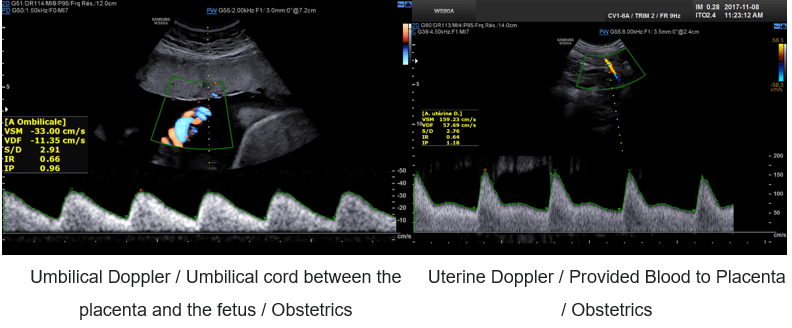

For example, pulsed Doppler is used in obstetrics to measure the flow of the umbilical and fetal arteries.

Color Doppler

What is Color Doppler?

Color Doppler converts the Doppler measurements into an array of colors. It is possible to obtain 2D or 3D velocity mapping by repeating the measurement at different depths.

In other words, the color Doppler technique estimates the average velocity of flow within a vessel by color-coding the information. The direction of blood flow is assigned by the color red or blue, indicating flow toward or away from the ultrasound transducer, and is superimposed on B mode data from stationary structures within the beamwidth. By convention, blood flow traveling toward the transducer is encoded in red, and blood flow moving away from the transducer is encoded in blue.

Examples of Images

Color Doppler is mostly used in fetal and hepatic ultrasound, where the primitive carotid and the hepatic vein are well visible.